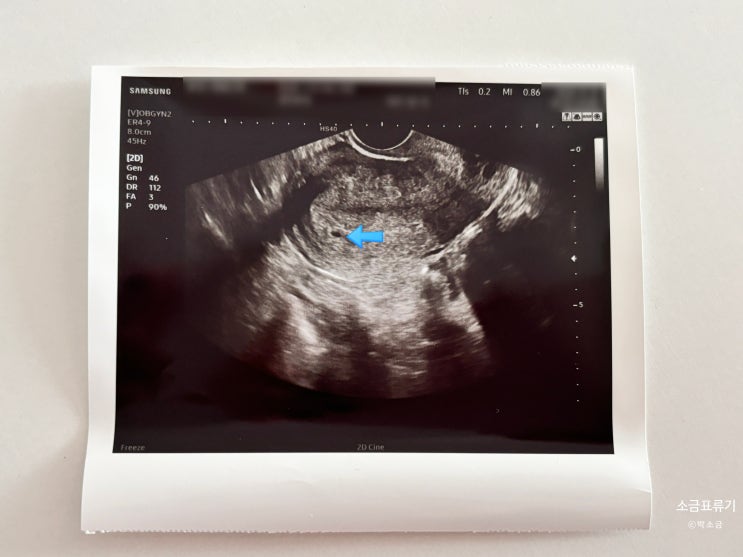

임신 3-4주 차 임테기 역전 아기집 확인 베이비아스피린 유산방지질정

하희루~ 저는 이번 임신을 굉장히 빨리 알게 되었는데요 빠르게 임신 사실을 알고 나서부터 느꼈던 증상과 ...